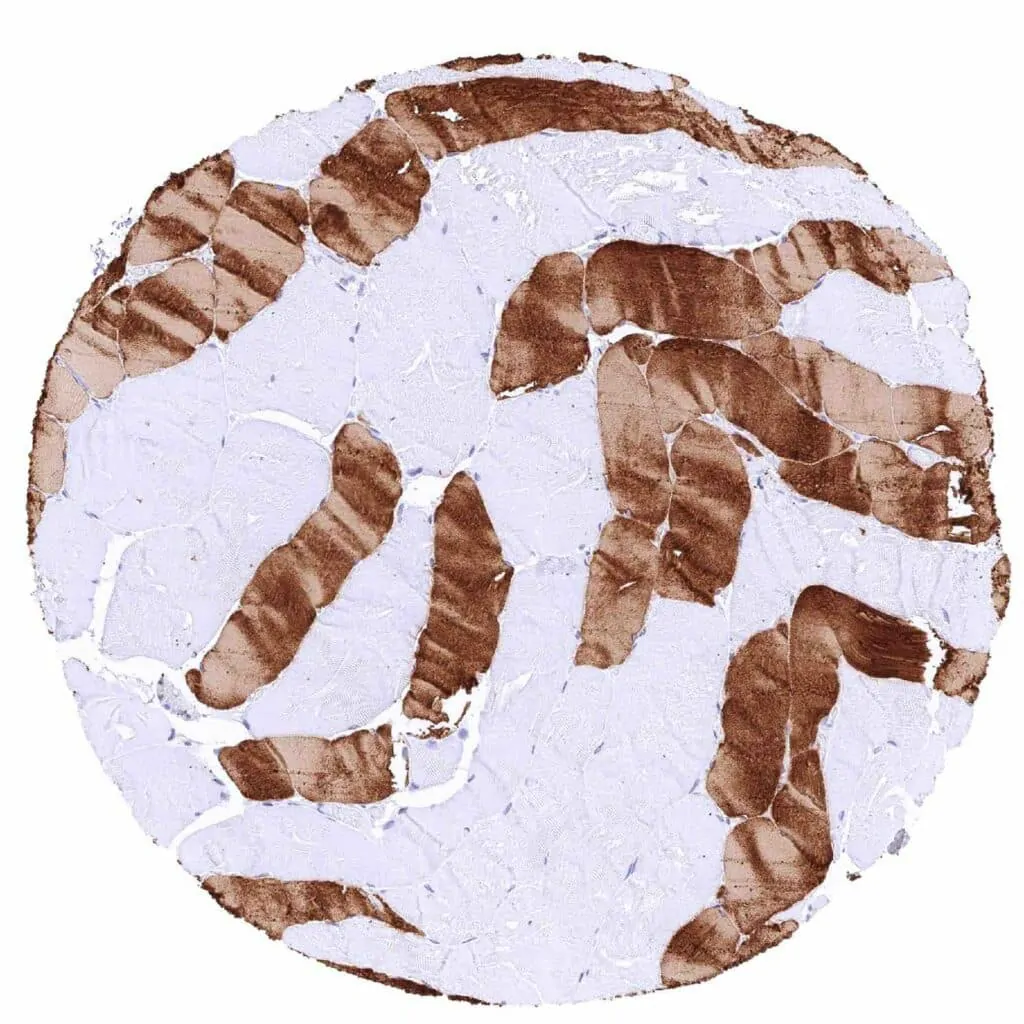

Heart muscle – Strong cytoplasmic MYH7 staining of all muscular cells